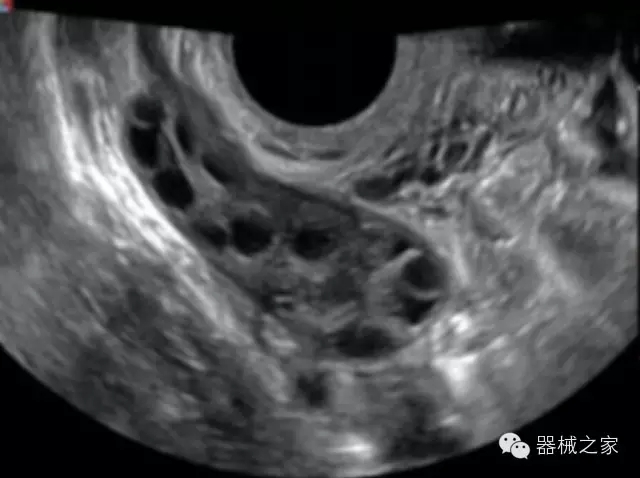

臨床圖片賞析

·獨有的RF平臺提高微小細節(jié)顯示、圖像對比度和邊界清晰度;

·特有的XCEN探頭,超寬的帶寬,表現(xiàn)更高分辨率和對比度;

·單晶純凈波探頭提供更佳的穿透力和彩色敏感度;

·完整的3D/4D臨床應用,STIC, MCUT 和Auto NT等滿足產(chǎn)科所有應用;

·更高的HQ羊膜腔鏡成像技術精細觀察每一個暗區(qū)細節(jié);